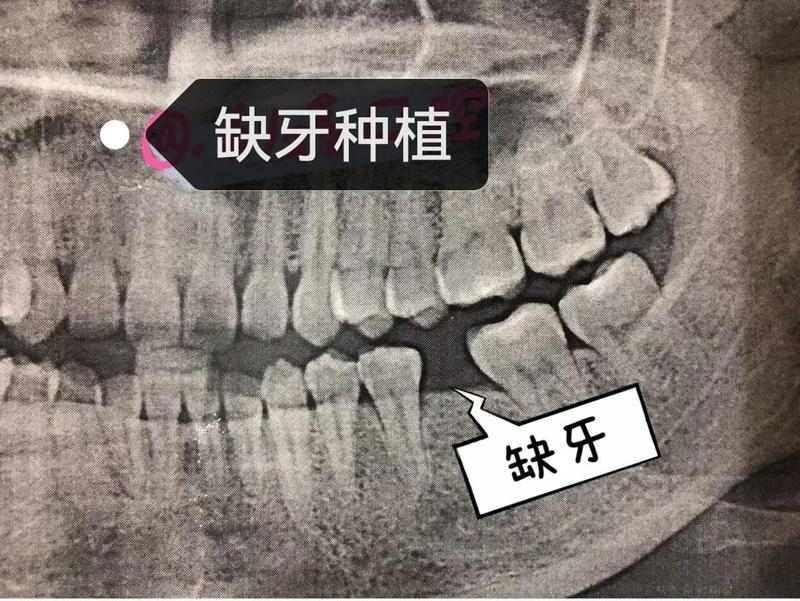

三、南通市第三人民医院口腔科牙齿种植真人案例分享

术前:我一直因为牙齿缺失而烦恼,不仅影响了美观,还影响了咀嚼功能。在经过多次咨询和了解后,我决定来到南通市第三人民医院口腔科进行牙齿种植手术。

术中:在面诊时,沈婷医师详细查看了我的口腔状况,并根据我的需求制定了适合的种植方案。手术过程中,医生们操作规范、细致,让我感受到了专业的医疗水平和服务态度。